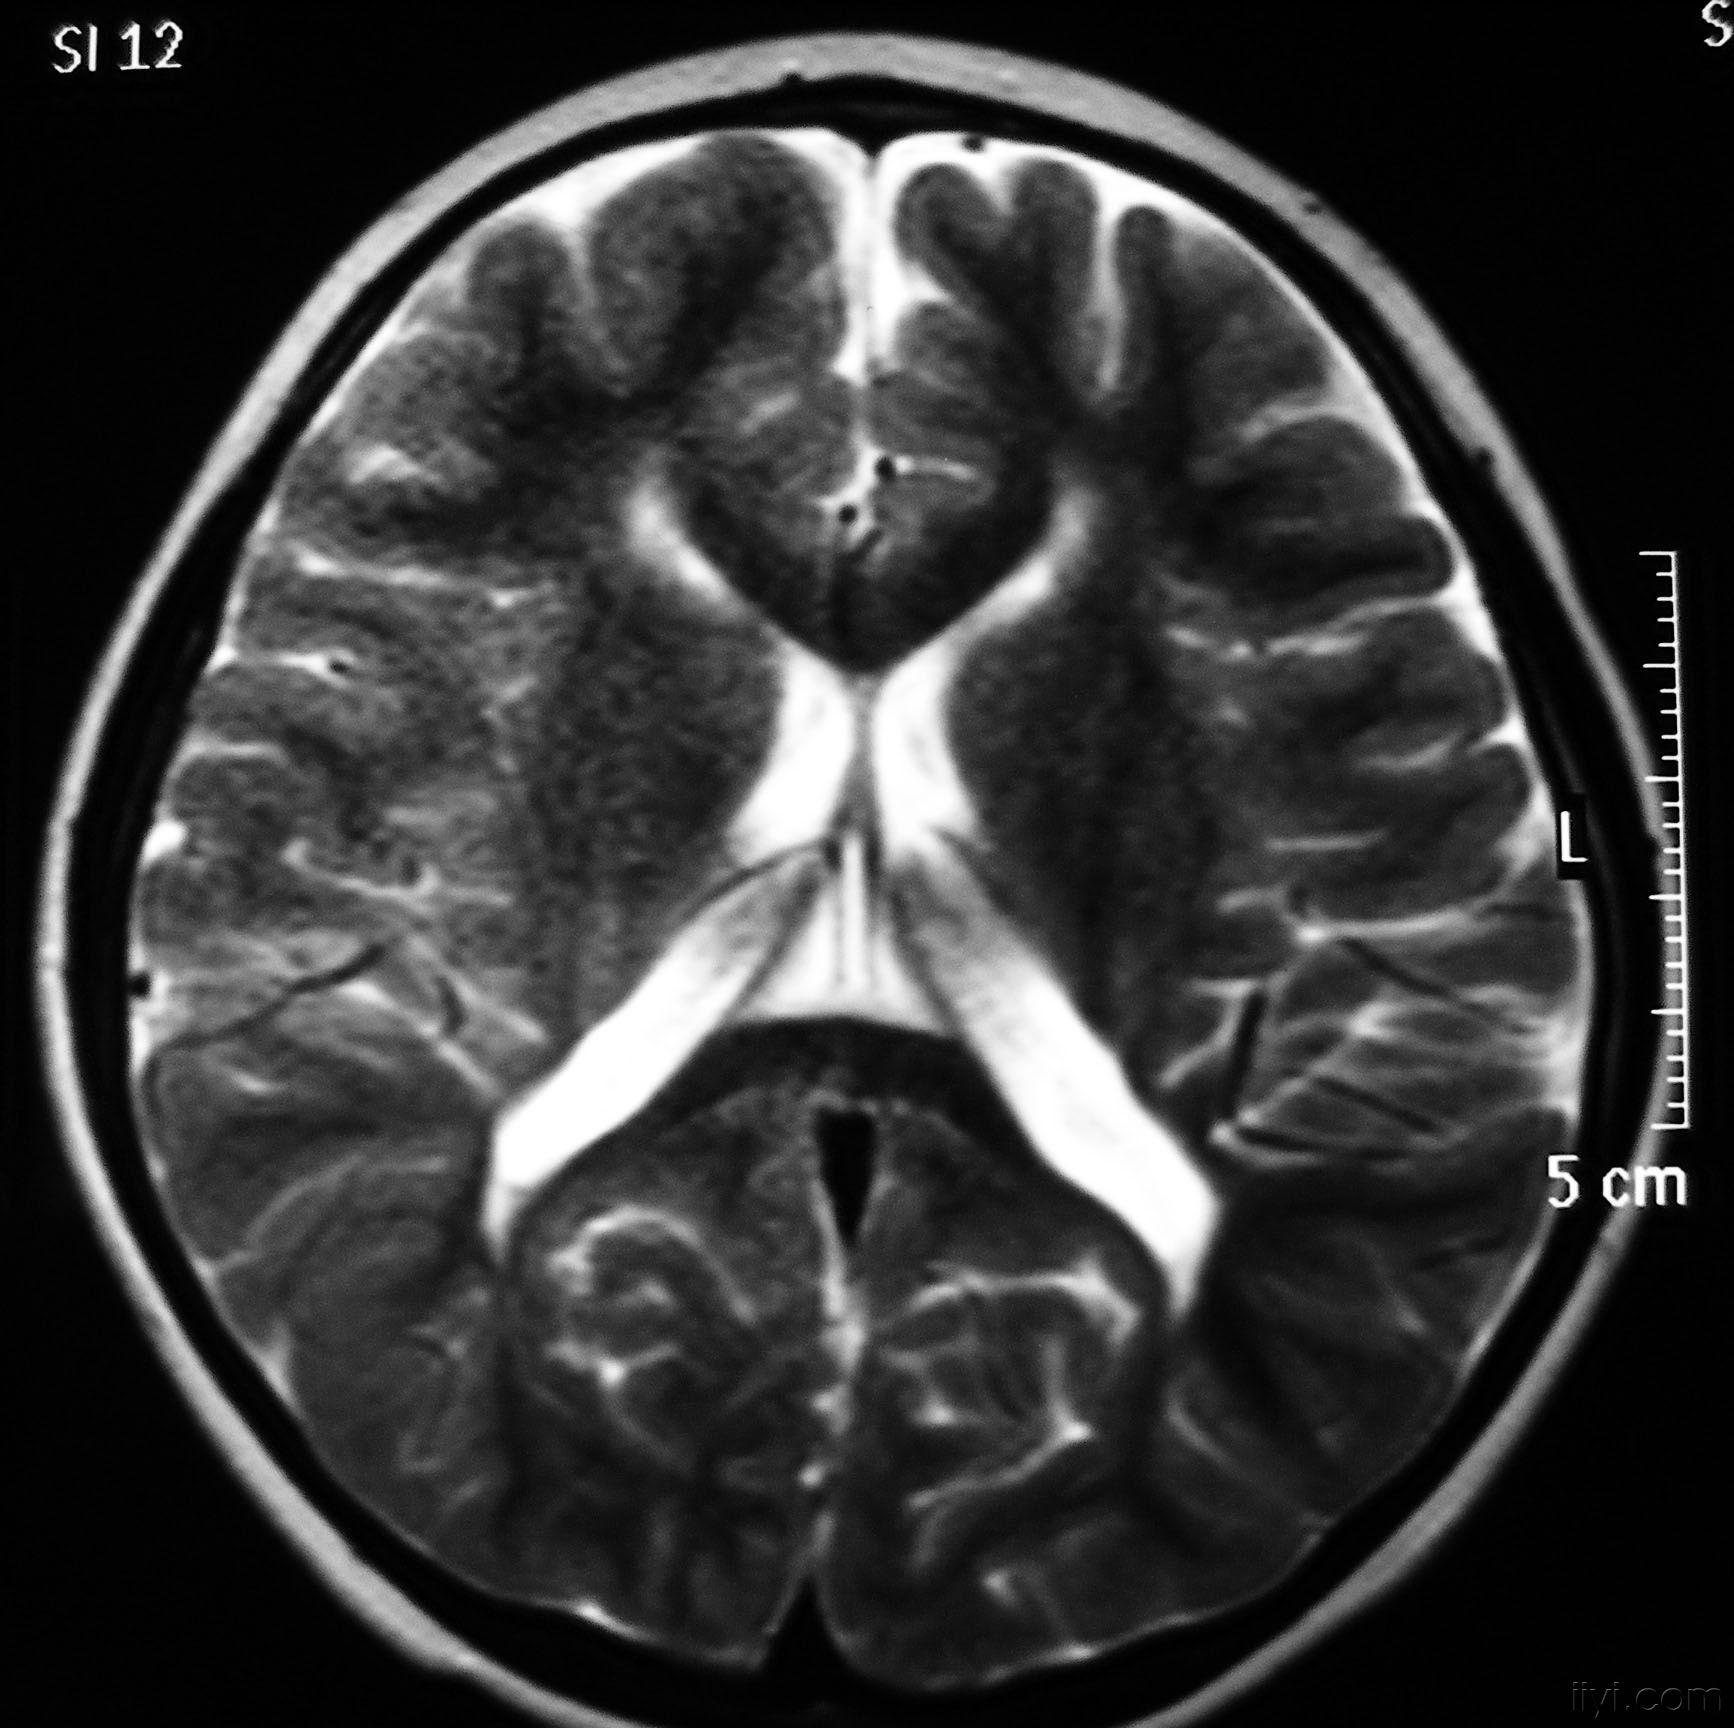

影像学发生于侧脑室周围,侧脑室扩大,脑白质减少。扩大的侧脑室外缘常不规则为其特点,多为双侧脑室同时扩大。脑白质减少,脑皮层与脑室侧缘相近。MRI T1呈低信号,T2呈高信号。